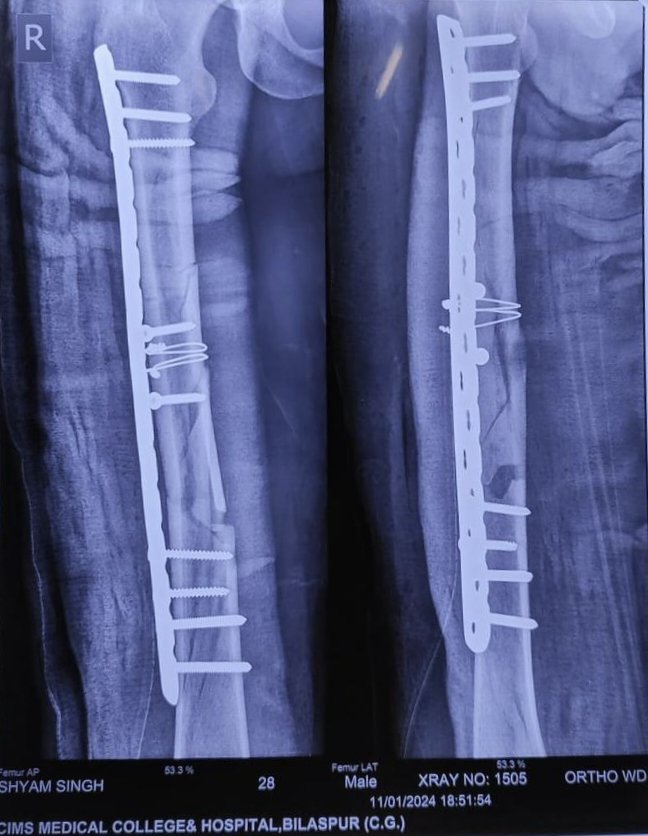

मरीज़ का ऑपरेशन विभागाध्यक्ष डॉ. ऐ.आर. बेन, डॉ. आर के दास, डॉ. राजीव सकुजा के मार्गदर्शन में डॉ. दीपक जांगड़े हड्डी रोग विशेषज्ञ के द्वारा 4 घंटे की जटिल सर्जरी जिसमें जांघ की हड्डी जो कई टुकड़ो में टूटी थी जिसे स्क्रू, वायर और प्लेट के द्वारा पहले की तरह जोड़ा गया। डॉ. दीपक ने बताया की ऑपरेशन के दौरान जांघ की हड्डी कई टुकड़ो में बट गई थी, जिसे वापस अपनी जगह में जोड़ना चुनौतीपूर्ण था। ऑपरेशन में करीब 18 होल लम्बे प्लेट का उपयोग किया गया है जो अपने आप में ही सबसे लम्बी प्लेट है जो सिम्स में पहली बार किसी ऑपरेशन में उपयोग हुआ है।